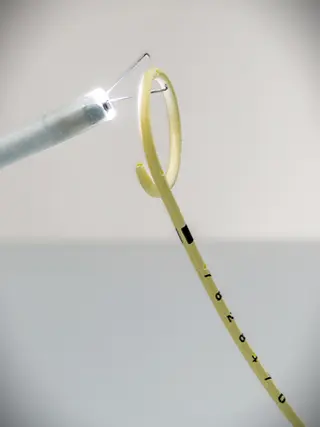

El retiro de un catéter doble J es un procedimiento médico que se realiza para eliminar un catéter que ha sido colocado en el tracto urinario para facilitar el drenaje de la orina desde los riñones hasta la vejiga.

Sin complicaciones

Indoloro

Rapida recuperacion